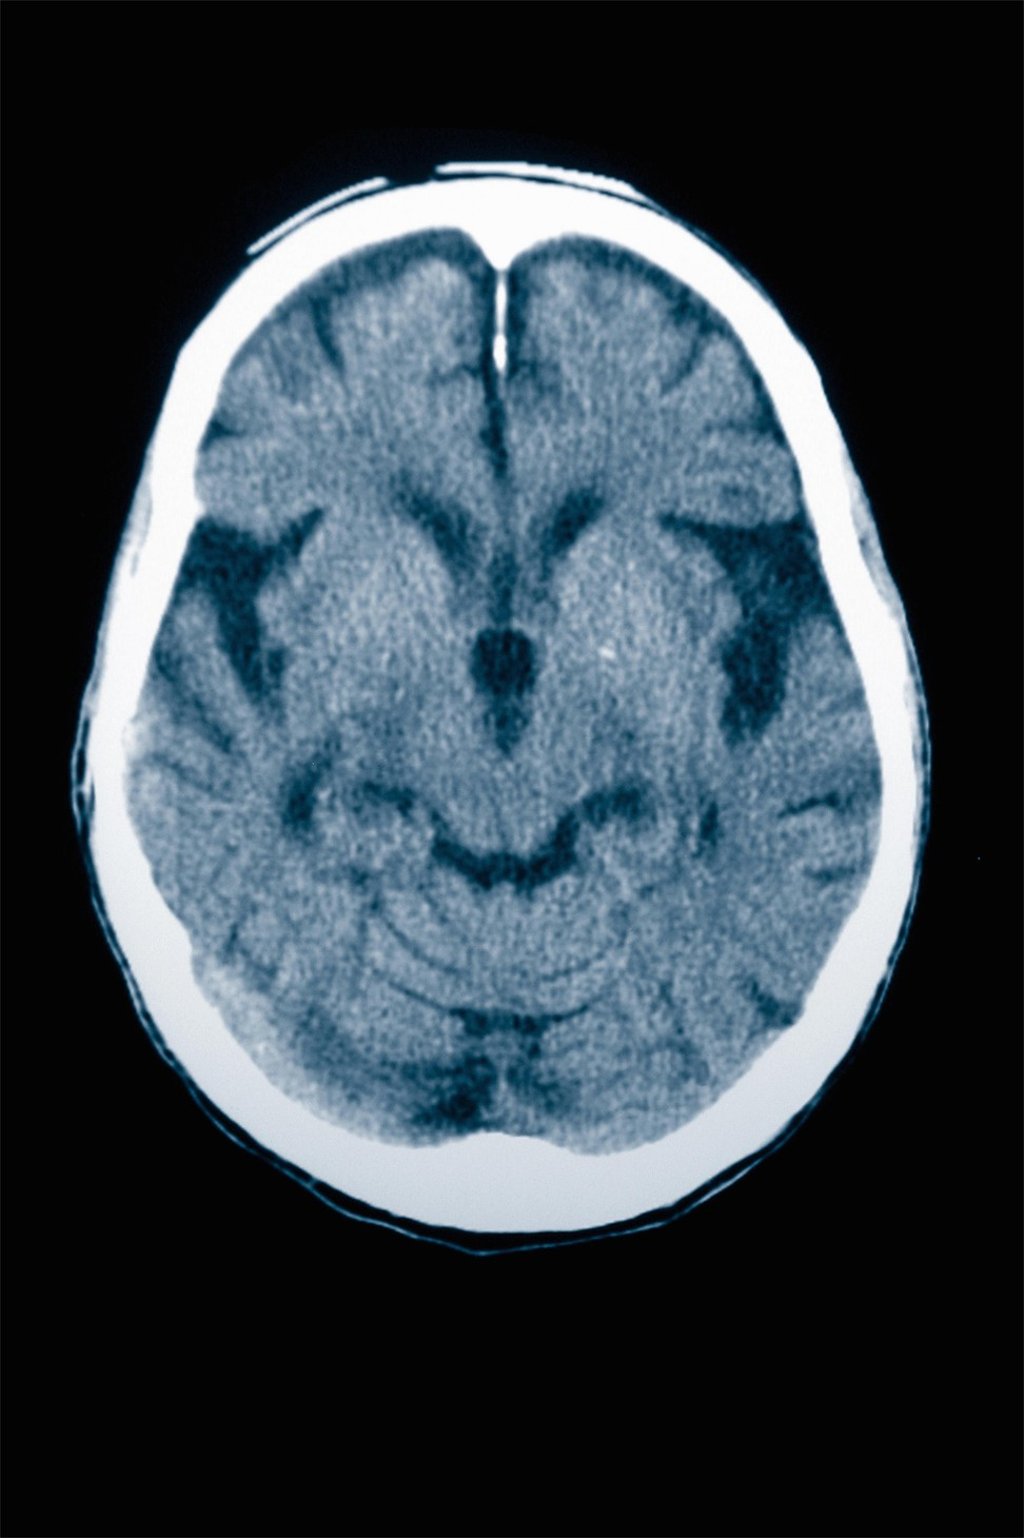

Removing harmful ‘zombie’ cells reduces Alzheimer’s impact in mice, raising hope for dementia prevention

Eliminating dead but toxic cells occurring naturally in the brains of mice designed to mimic Alzheimer’s slowed neuron damage and memory loss associated with the disease, according to a study that could open a new front in the fight against dementia.